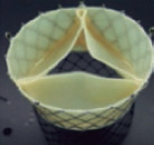

Valve replacement devices

The transcatheter replacement of the TV can be orthotopic or heterotopic. The first experiences with this technique used aortic valves for percutaneous implantation in the tricuspid position. The “valve-in-valve” or “valve-in-ring” percutaneous implantation of an aortic valve in the tricuspid position is more common. Acceptable short-term results with these procedures have been reported.23 However, the development of transcatheter tricuspid valve replacement systems in native TV is much more interesting.

GATE

The GATE bioprosthesis (NaviGATE Cardiac Structures, Lake Forest, CA, United States) is the only device available today experienced clinically in humans as compassionate use. Also, it is the only device that allows fully orthotopic transcatheter tricuspid valve replacements. It is a xenopericardial leaflet bioprosthesis inserted into a self-expandable nitinol scaffold. The nitinol stent is wider in the ventricular region, giving it a tronco-conical morphology that reduces the transvalvular gradient and minimizes the outflow tract obstruction (since very little material protrudes towards the ventricle). It can be implanted using the jugular approach or the right atrium through minithoracotomy; the femoral access is still under development. The necessary size for the jugular access is ≥ 14 mm because a 42-Fr introducer sheath is used. In both cases, at least 7 cm are necessary from the annular entry site to steer the device (which should be angulated 70º) so that it is perfectly coaxial to the annular plane.

The prosthesis is available in 5 different sizes (36 mm, 40 mm, 44 mm, 48 mm, and 52 mm). A slight oversizing (from 5% to 10%) with respect to the annular dimensions is advisable. To select the device size, it is required to measure the annulus using TEE and computed tomography scan. On the CAT scan, the distance between the annulus to the right coronary artery is a very important feature to avoid damage and have guidance during the procedure. The x-ray projection imaging of the implant is also derived from the CAT scan.

To this day, very few implants have been performed worldwide and always with compassionate use. Recently, the experience of the University of Columbia with 5 consecutive procedures has been published.24 Procedural success was 100% and the route of access was minithoracotomy in all cases. Only 1 patient died within the first 30 days after the procedure. Successful implantation was associated with improved RV remodeling, increased cardiac output, and a better NYHA functional class in most patients.